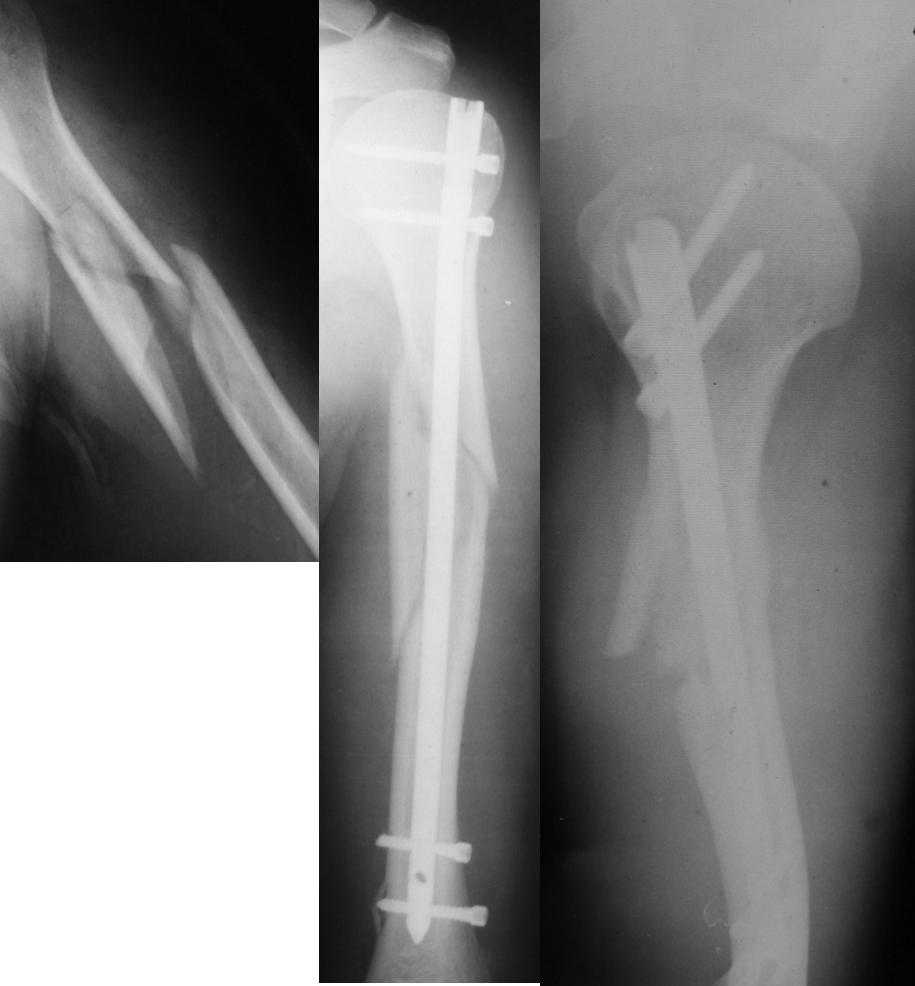

Уважаемые коллеги! Необходима консультация.Больной 52 лет.Травма 02.10.2007г.Операция-19.10.2007г.

Сразу после операции-нарушения кожной чувствительности по наружной поверхности н\3 предплечья,кисти,1 и 2 пальцев кисти,ограничение активных движений в лучезапястном суставе при сжатом кулаке.При электромиографии-лучевой нерв 4% от нормы. Через два месяца после операции беспокоят боли в месте перелома в покое и при движениях в плечевом суставе. Отсутствие положительной динамики в восстановлении кожной чувствительности и объеме движений в л-з суставе.Дальнейшая тактика-ждать?, оперировать? Спасибо.

Лучевой нерв контузили скорее всего при введении нижних винтов. Коллегам доводилось встречать даже дефект лучевого нерва в результате его наматывания на сверло, поэтому в дистальном отделе плеча безопаснее вводить винты в сагиттальной плоскости.